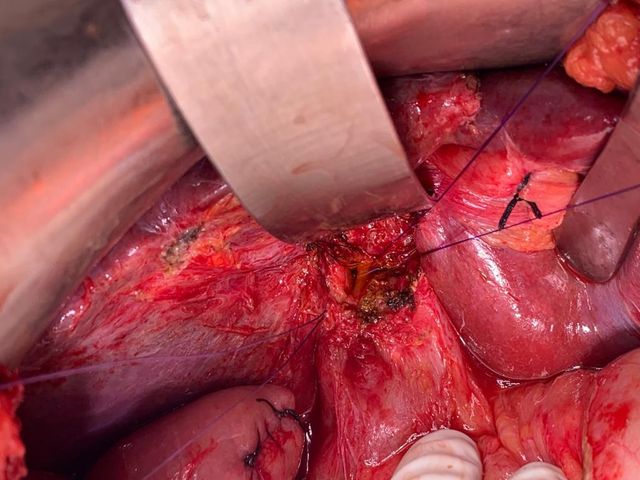

Patient with Type - 3 B hilar cholangiocarcinoma was admitted with obstructive jaundice

Patient with Type - 3 B hilar cholangiocarcinoma was admitted with obstructive jaundice. His bilirubin was 15 mg%. He had an attempted ERCP outside which failed so underwent a Rt PTBD. He was readmitted for surgery after 3 weeks with a bili of 2 mg%. At diagnostic lap he had evidence of PtBD catheter displacement with bile leak but as patient was not septic he went ahead with an extended left hepatectomy with enbloc caudate lobectomy and bile duct excision and right hepaticojejunostomy to separate Rt anterior and Rt posterior.